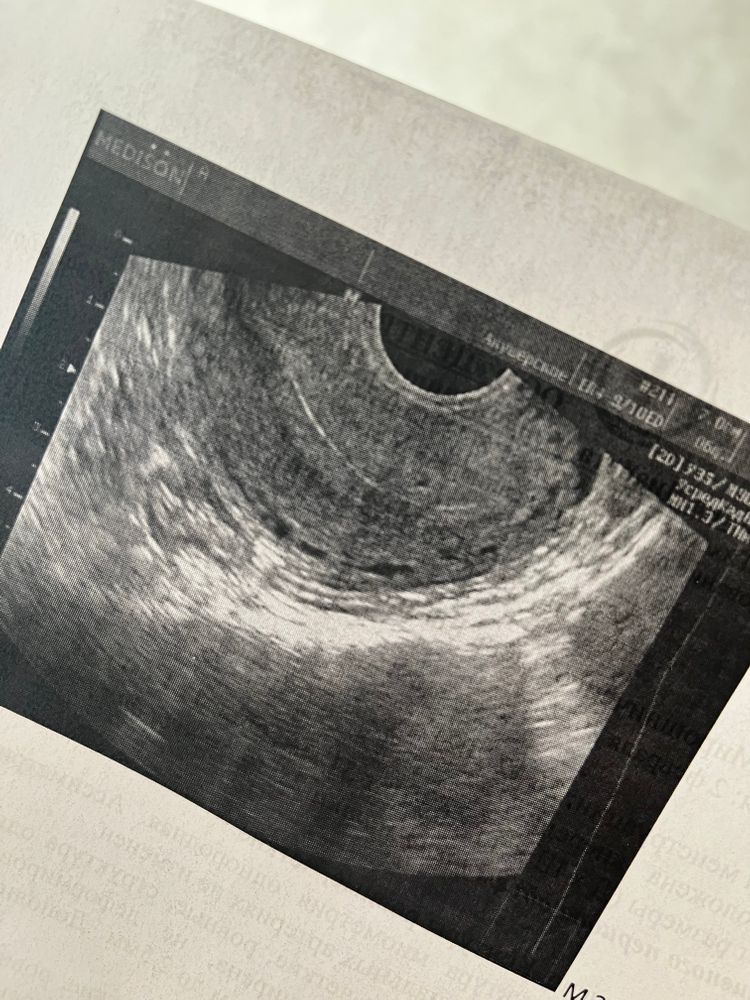

Наиля , мне вот искала тоже минут 10, сказала 2мм что-то есть, но утверждать не будет.

Пара гематом никого не смущает?видно и пя и их..